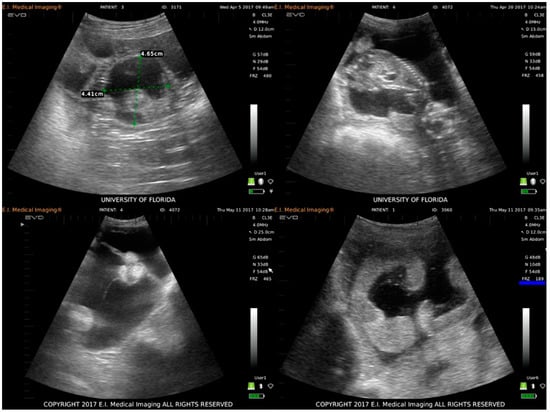

3.1. Clinical Disease and Fetal Development